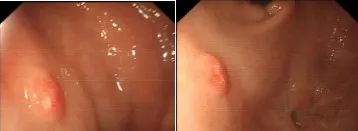

一次普通的無痛胃鏡檢查,竟救了七旬老人一命,說起這個事兒來現(xiàn)在躺在病床上,做完內(nèi)鏡ESD微創(chuàng)手術(shù)的劉大叔,突然有種劫后重生的感覺,他激動地說:要不是做了這次胃鏡,恐怕就發(fā)展成胃癌了,家住本市的劉大叔身體硬朗,平時也較注意身體保健,近日,總在一起下棋的老朋友,在胃鏡體檢檢查中發(fā)現(xiàn)了數(shù)十枚胃息肉,這讓劉大叔心中也泛起嘀咕,在老朋友的建議下,他來到國文醫(yī)院開具了胃腸鏡檢查,一向身體硬朗的劉大叔生平還是第一次行全身麻醉,迷迷糊糊就睡過去了,醫(yī)生開始緩慢進鏡,腸鏡一切順利未有異常,而在胃鏡過程中發(fā)現(xiàn),胃體上部見一大小約0.6*0.6cm隆起糜爛灶,中央色紅、略凹陷,取活檢1塊。